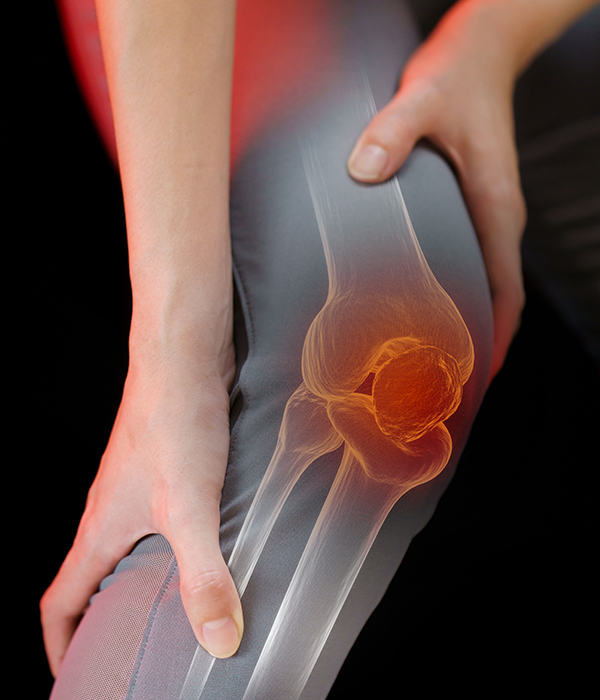

프롤로테라피

프롤로테라피는 증식(Proliferation)과 치료(Therapy)가 합쳐진 말로 손상된 연골, 뼈, 인대, 힘줄 부위의 기능을 회복 시켜줄 수 있는 주사 치료방법입니다.

도수치료

근골격계 질환의 증상을 개선하기 위한 비수술 치료방법으로, 전문 물리치료사가 손을 이용해 척추나 사지의 연부 조직, 관절의 위치를 바로잡고 통증 및 체형을 치료하는 방법

체외충격파치료

체외충격파는 음속보다 빠르게 몸속으로 전달되는 압력 파동을 의미하며 통증을 일으키는 부위에 적정 주파수와 에너지를 선택하여 2000회 이상의 충격파를 쏘는 비침습적 치료법입니다. 최근 활발한 연구가 이루어 지고 있는 분야이며 그 효과가 수많은 논문들에서 입증되고 있습니다.